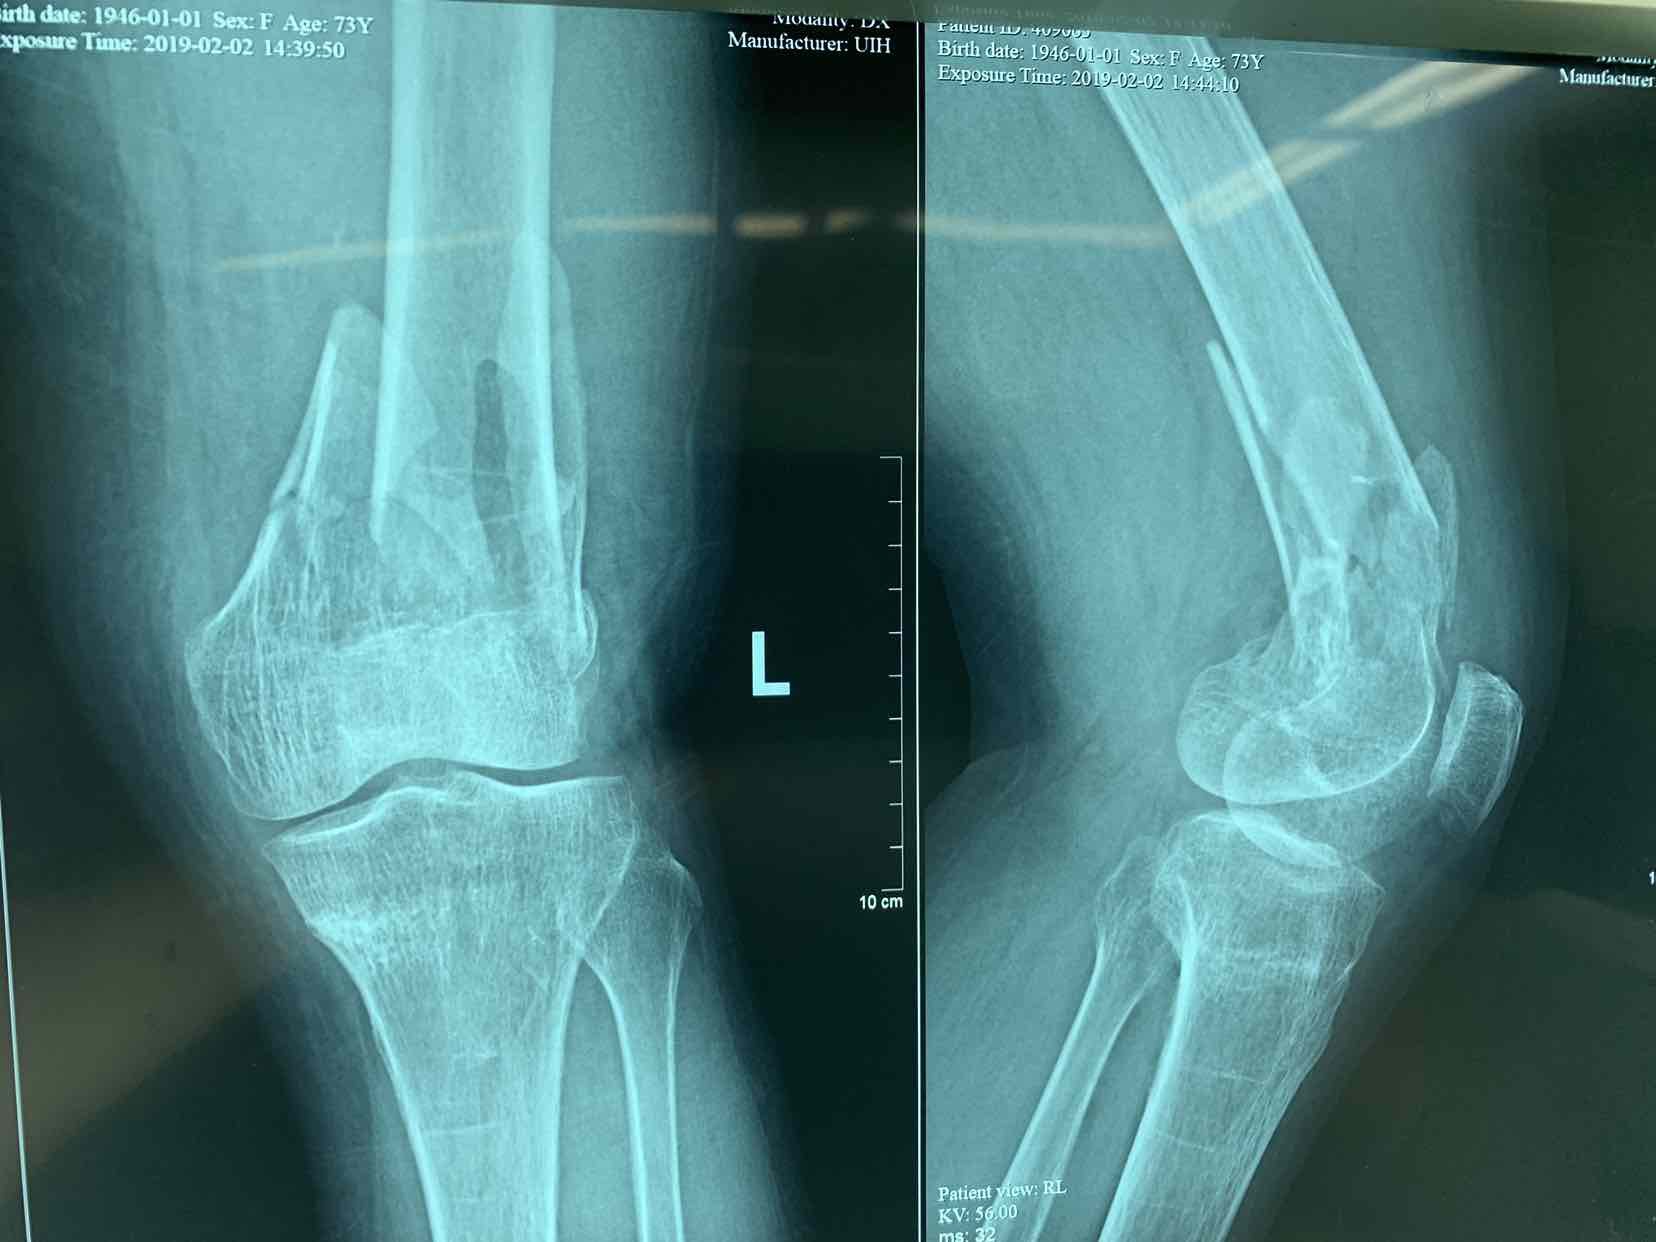

患者因左侧膝部摔伤,肿痛。畸形,活动受限一小时收入院。患者平时活动较差,有脑梗塞病史,下地活动困难,今天在一小时前下地活动时摔伤,当即左侧膝部肿胀,畸形,局部异常活动。立即来诊,拍片提示左侧股骨髁上粉碎性骨折。门诊以左侧股骨髁上粉碎性骨折收入院治疗。

查体见患者左侧膝部肿胀,局部畸形,活动受限,🈶️异常活动,足背动脉搏动减弱,足趾活动自如,拍片提示左侧股骨髁上粉碎性骨折,对位欠佳,。